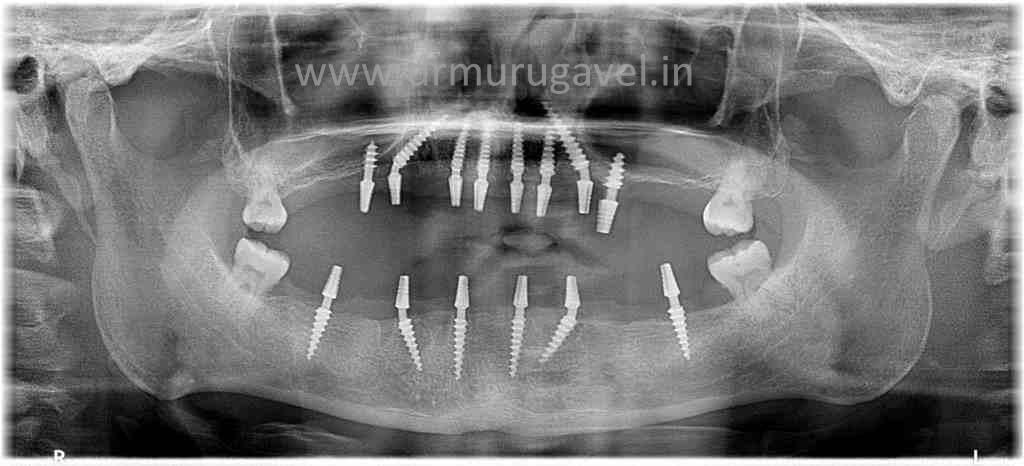

This patient was 55 year old with many teeth missing and also few existing remaining teeth which are weak .

We planned for full mouth rehabilitation with basal dental implants and compressive dental implants

and fixed teeth cemented in 3 days..

POST IMPLANT XRAY